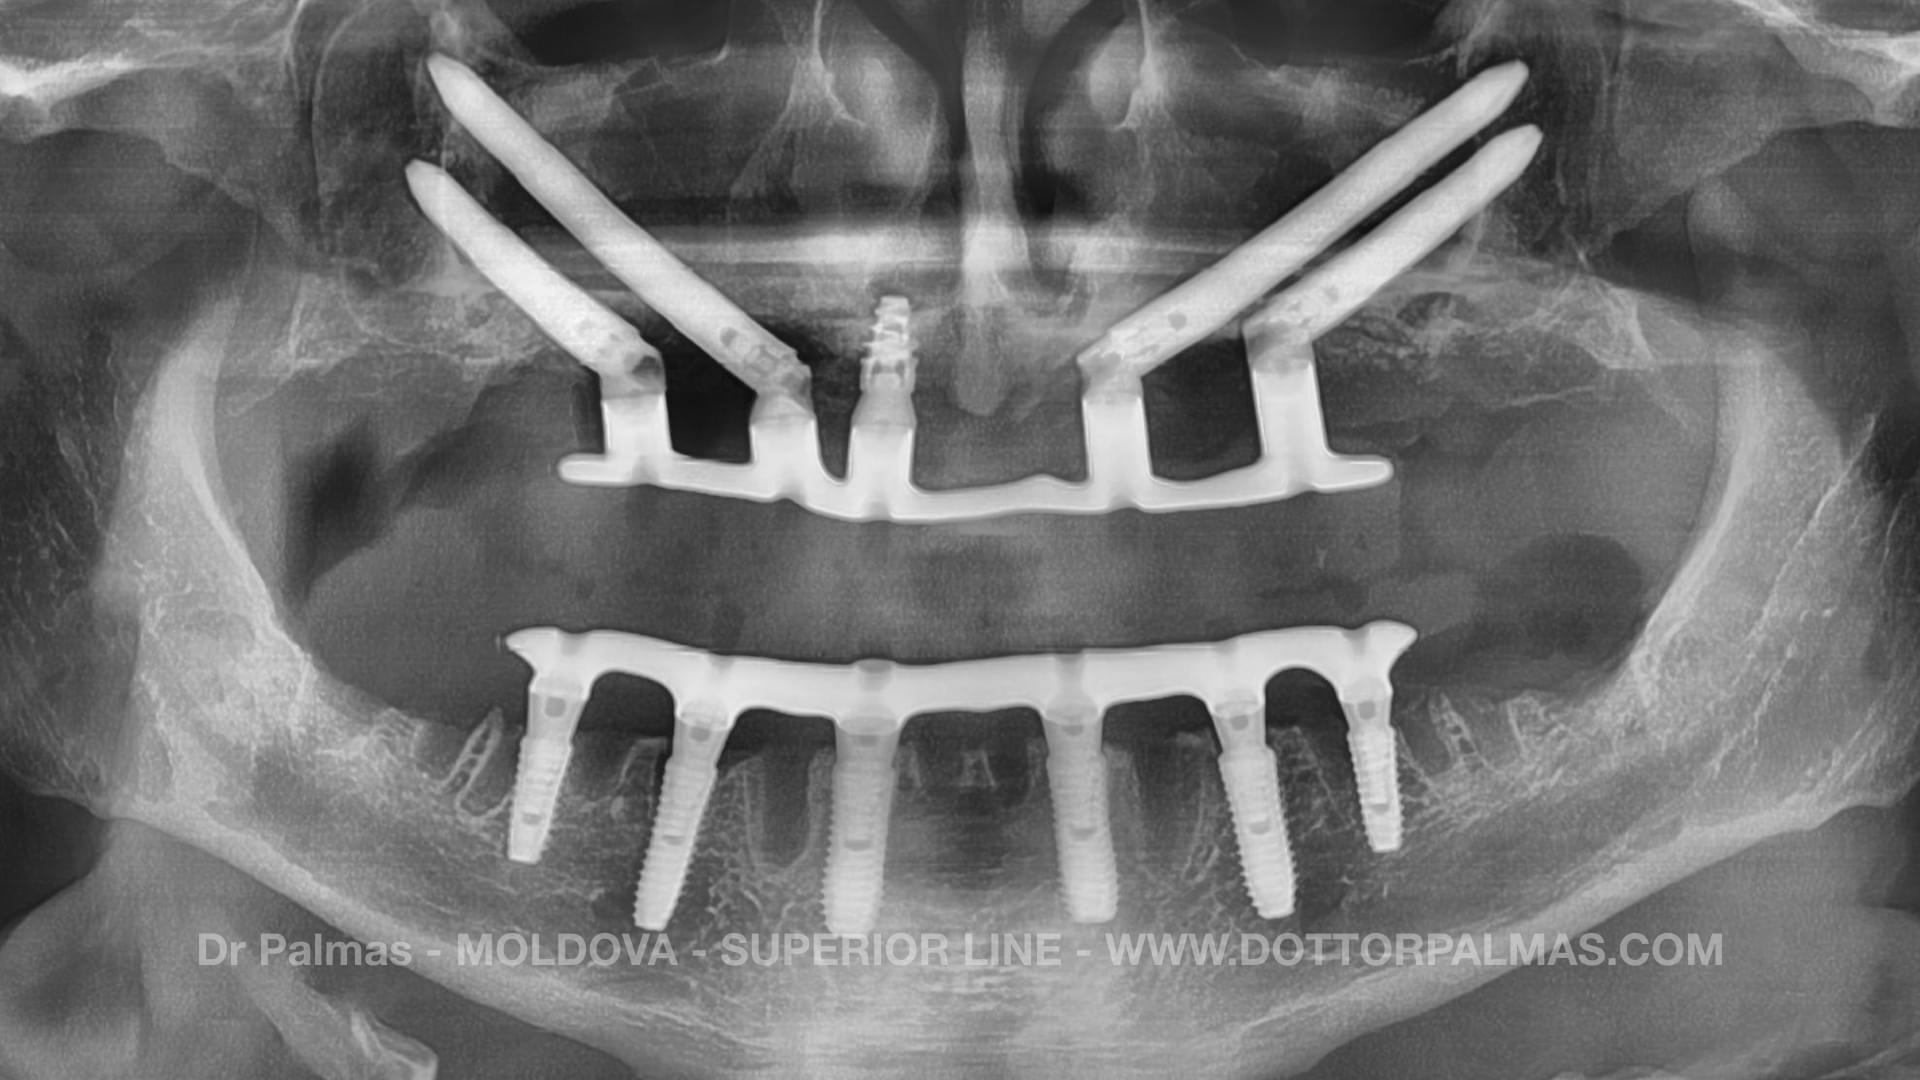

Un Paziente che ha eseguito una Chirirgia Estrema di Impianti Zigomatici

COSA SONO GLI IMPIANTI ZIGOMATICI?

Gli Impianti Zigomatici sono una categoria di impianti dentali NON CONVENZIONALI che permettono di ri mettere i denti fissi a quei pazienti su cui hanno fallito impianti convenszionali.

Se un Dentista ti ha detti che NON HAI OSSO probabilmente il tuo potrebbe essere un caso da Impianti Zigomatici.

Ogni intervento chirurgico eseguito dall'Equipe del Dr Palmas viene pianificata partendo dalla TAC 3D del paziente.

• Equipe Maxillo Facciale: Non semplici dentisti, ma Chirurghi di Sala Operatoria

• Anestesia Generale: Per i casi che lo richiedono, come Impianti Zigomatici possiamo addormentare completamente il paziente come all'ospedale